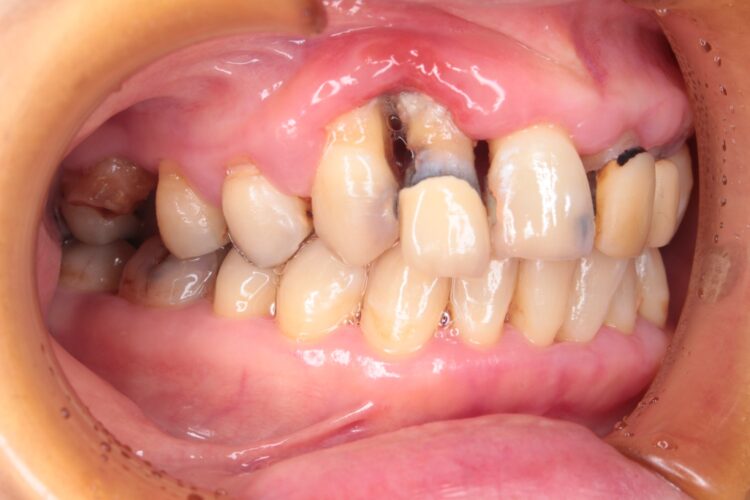

ご自宅でのケアを継続していただいた結果、初診時と見違える程歯ぐきの腫れが改善してきました😊

現在の歯の状態は、

腫れは引いても、骨が無いのでエアーをかけただけでグラグラする、

少し触っただけで出血をし、歯石が突起の様に飛び出して歯茎に突き刺さっていました。

歯磨きするのが本当に難しい状態でしたが、ここまで頑張って綺麗にしていただけたおかげで、いよいよ歯石を除去する事ができます。